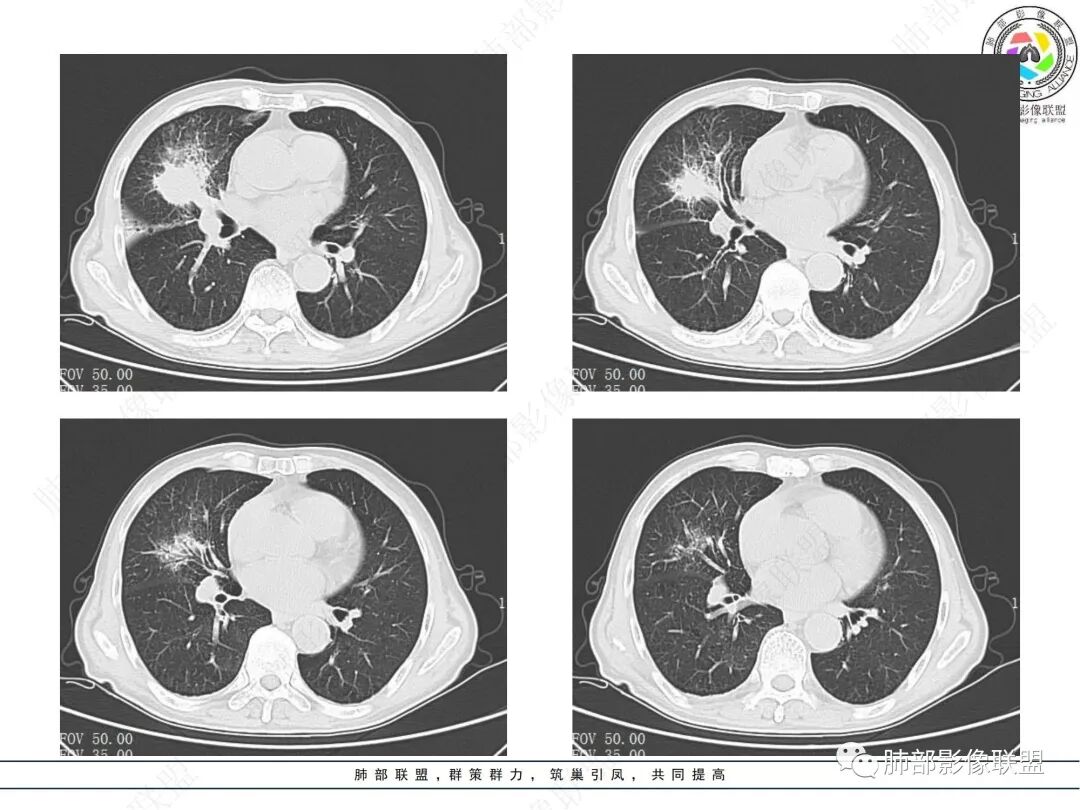

晨读病例,老年男性,乏力,纳差,近来发热,右肺上叶团片状阴影,内见空洞,空洞内壁不光滑,见短液平,增强病灶壁可见不均匀强化,似有边界不清晰的坏死,病灶周围可见片状模糊阴影,考虑恶性病变,鳞癌或腺癌伴感染。

老年男性,肺气肿背景,右肺较大分叶状肿块,密度不均,内坏死空洞形成,坏死区边界不规则,周围多发斑片蜂窝状、网格状高密度影,考虑鳞癌合并感染

右肺上叶及中叶不规则肿块伴周围模糊影,其内小叶间质结节样改变,肿块不均匀强化,坏死及空洞,坏死边界不清,血管显示尚可,考虑腺癌,鉴别淋巴瘤

老年男性,有咳嗽发热。右肺中上叶团状软组织肿块,周围磨玻璃渗出改变,病灶内密度不均,可见低密度坏死及空洞影,空洞内壁凹凸不平,近肺门侧可见明显大面积坏死。近端支气管堵塞不明显。考虑恶性肿瘤伴感染,腺癌?鉴别鳞癌,感染性病变。

右肺上叶团片状阴影,内见空洞,空洞内壁不光滑,偏心,,增强不均匀强化,内有边界不清晰的坏死,病灶周围可见片状模糊阴影,右下肺也有磨玻璃病灶,Crp高,腺癌

70岁男性,发烧病史,右肺巨大肿块,边缘分叶,内部空洞,洞内见附壁结节,局部支气管阻塞,肿块周围见大片阻塞性炎症;实验室检查,炎性指标增高;考虑恶性肿瘤伴阻塞性肺炎,鳞癌可能。

老年男性,乏力,纳差,发热。右肺上叶团片状阴影,密度不均,可见低密度坏死,坏死边界不清,可见空洞形成,见短液平;增强病灶呈不均匀强化,其内血管边缘模糊毛糙;病灶周围可见斑片状渗出病灶,支气管未见明确阻塞。综上考虑肺癌伴感染,鳞癌可能。

老年男性,纳差和发热,炎症指标明显。右肺磨玻璃影伴有肿块,肿块呈膨胀性生长,内部没有气管影。首先考虑感染,并有肿瘤的表现。考虑鳞癌合并感染

右肺上叶实变,密度不均,内可见小气液平,周磨玻璃影,斜裂稍内凹,右下肺可见斑片影,强化可见血管走行自如,右侧胸腔少量积液,考虑感染性病变,努卡?放线菌?

老年男性,肺气肿背景,右肺上叶及中叶大范围实变影,边界不清,支气管通畅,其内见边缘膨隆软组织块影伴不规则坏死、空洞,增强扫描不均匀强化,洞壁显示不清,血管稍变细,实变影内另见多发囊样影,右肺下叶小片状影,病灶跨叶,炎性指标增高,感染应该有的,不除外合并恶性肿瘤(鳞癌?腺癌?)

男,70,反复乏力、纳差20天,发热1天。胸部CT:肺气肿背景,右肺上叶中叶大团片影,实变十磨玻璃渗出。增强实性斑片影内密度不均,可见多发低密度坏死及不规则空洞影,空洞内壁尚光滑,血管边缘模糊。支气管管壁增厚,管腔通畅。右下叶可见小片渗出影。考虑支气管肺炎进展?病原考虑能形成肉芽肿、坏死空洞的微生物,TB?奴卡?鉴别鳞癌。

老年男性,乏力纳差,进食量明显下降,发热,后期少许黄脓痰,无咯血。无胸痛。未提口腔卫生情况,发热时间段不明确,肺气肿背景,气管内痰拴还是其他?觉得是外朝内进展病灶,右肺多叶段病灶,支气管通畅,支气管壁弥漫增厚,实变病灶内有坏死,坏死边界比较清晰,血管破坏不明显,周围散在磨玻璃,边界模糊,无树芽,实变内可疑小钙化,右侧胸水,肺门纵隔淋巴结无明显肿大。病史不太支持化脓菌感染,真菌里隐球强化不太支持,结核需要排除,厌氧菌感染带排,冠状位矢状位病灶觉得类圆形,临床肿瘤也是不能轻易排除的